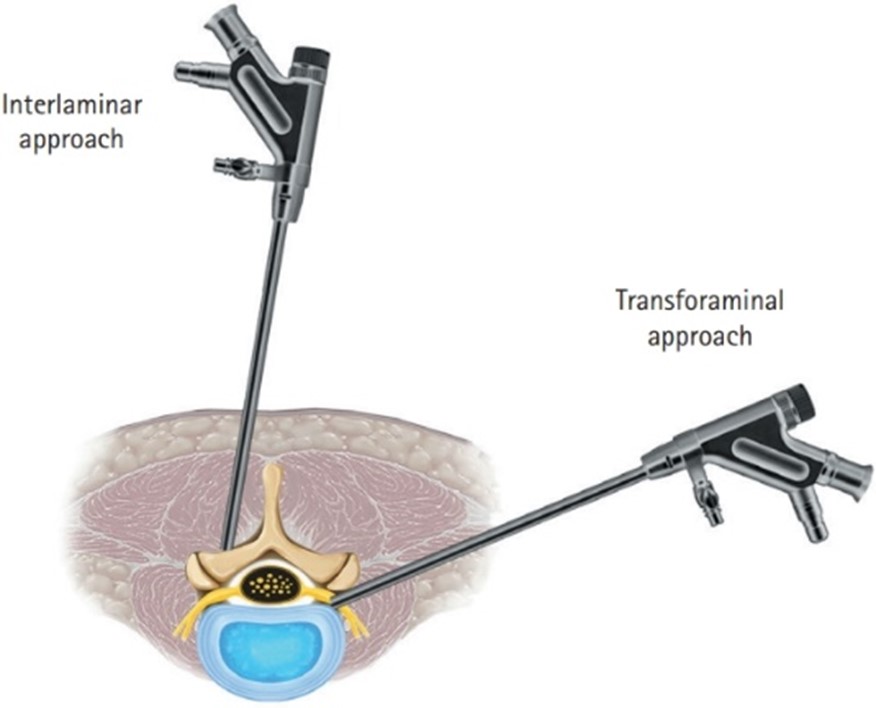

What are the techniques of uniportal spine endoscopy?

There are two standard techniques of spine endoscopy, transforaminal technique and inter-laminar technique. Both of these are techniques are of uniportal spine endoscopy. Any of these two techniques can be used depending on location of diseased structure and extend of decompression required.

- Transforaminal spine endoscopy

- Transforaminal endoscopy is so named because here we access the spine through the natural orifice in the spine called the ‘intervertebral foramen.’

- It used to target unilateral foraminal or extraforaminal or lateral recess disc prolapse or isolated stenosis of these regions.

- This surgery is done under local anaesthesia, that means the patient is totally awake during the surgery and can talk to the doctor during the procedure in case any discomfort is felt.

- Therefore this technique is good for morbid patients who are not fit for general anaesthesia.

- Interlaminal spine endoscopy:

- Interlaminar spine endoscopy is so named because here the spine is accessed through another natural orifice in spine called the ‘inter laminar window.’

- It is used for ligamentum flavum pathologies of central canal or lateral recess, central disc pathology or bilateral extraforaminal, foraminal or lateral recess pathology.

- The surgery is done under general anaesthesia.